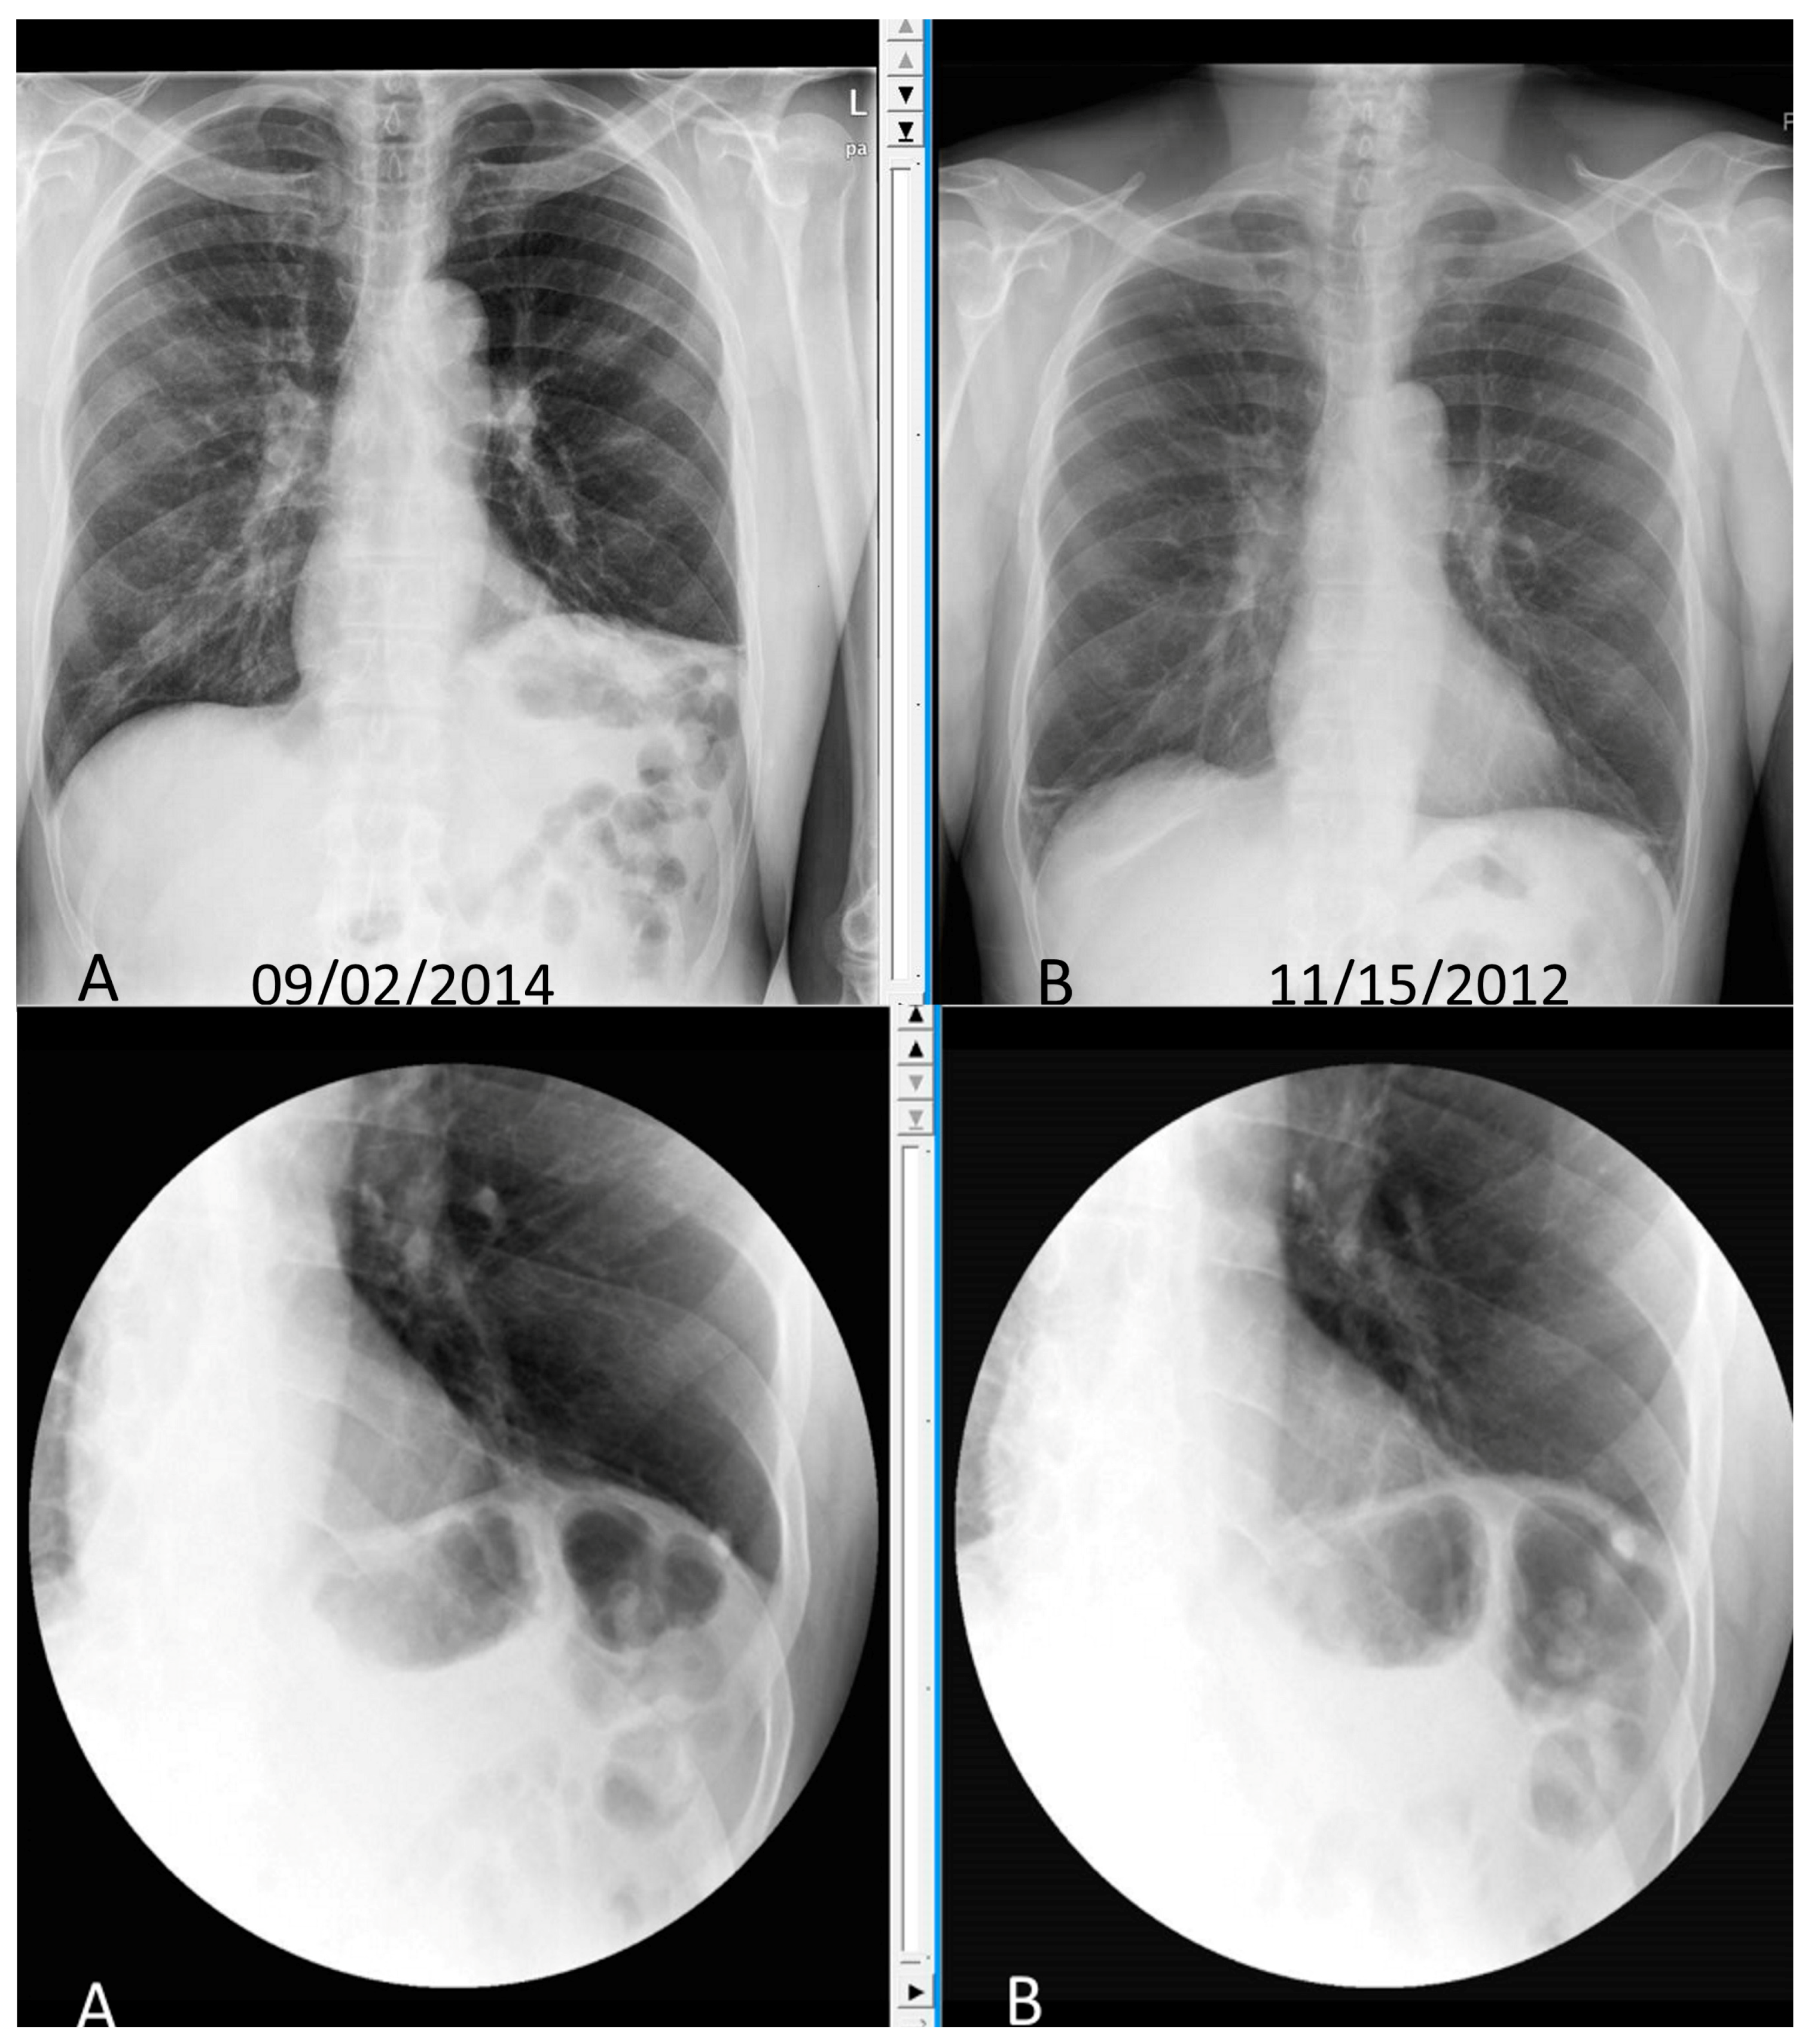

- Piehler, J.M.; Pairolero, P.C.; Gracey, D.R.; Bernatz, P.E. Unexplained diaphragmatic paralysis: A harbinger of malignant disease? J. Thorac. Cardiovasc. Surg. 1982, 84, 861–864. [Google Scholar] [PubMed]

- Chetta, A.; Rehman, A.K.; Moxham, J.; Carr, D.H.; Polkey, M.I. Chest radiography cannot predict diaphragm function. Respir. Med. 2005, 99, 39–44. [Google Scholar] [CrossRef] [PubMed]

- Nason, L.K.; Walker, C.M.; McNeeley, M.F.; Burivong, W.; Fligner, C.L.; Godwin, J.D. Imaging of the diaphragm: Anatomy and function. Radiographics 2012, 32, E51–E70. [Google Scholar] [CrossRef] [PubMed]